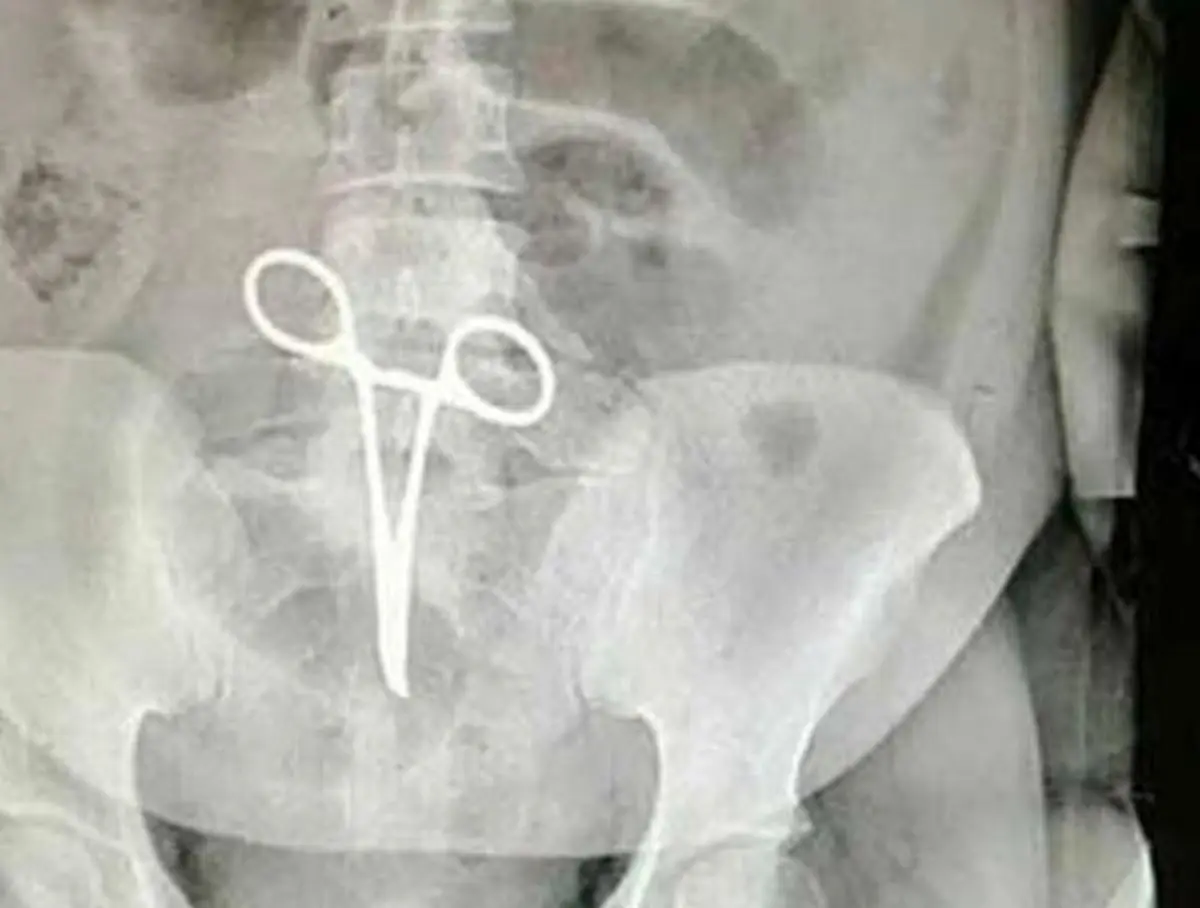

وی بابیان اینکه اشتباه رخ داده یکی از موارد نادر پزشکی بود که تاکنون در این بیمارستان اتفاق نیفتاده بود، افزود: بعد از اینکه عکس از ناحیه شکم بیمار گرفته می‌شود همکاران متوجه جسم خارجی(پنس) در داخل شکم بیمار می‌شوند.

رئیس بیمارستان شهید بهشتی اردستان، ادامه داد: بدون هیچ فوت وقتی مقدمات عمل جراحی سوم انجام می‌شود و عمل جراحی و عملیات بیرون آوردن پنس توسط پزشک جراح که این بیمار را عمل کرد انجام می‌شود.

رئیس بیمارستان شهید بهشتی اردستان در جواب سؤال مبنی بر اینکه پنس داخل شکم بیمار آیا باعث ضربه زدن به ناحیه داخل شکم بیمار هم شده است، افزود: باید توجه داشته باشیم که این‌گونه اتفاقات هیچ آسیبی به بیمار نمی‌رساند. متأسفانه خبرهایی که به اشتباه درباره این موضوع انتشار پیدا کرد یک دروغ رسانه‌ای بود. البته بابت این اتفاق از مردم عذرخواهی می‌کنیم.